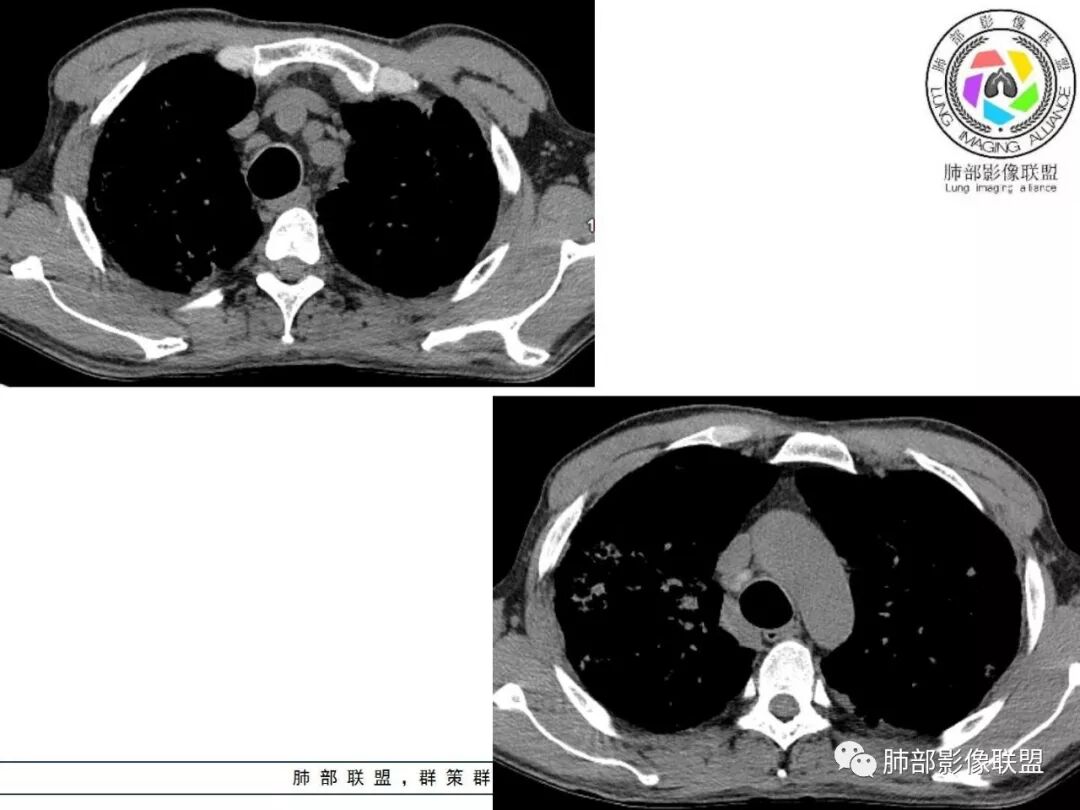

胸部CT:两肺弥漫病灶,磨玻璃影,少许实变,部分累及胸膜,磨玻璃区可见囊?少许胸腔积液,两肺可见结节,支气管血管束增粗,小叶间隔增厚,支气管走形有扭曲扩张,可见纤维化。气肿、大泡。考虑:感染性病变,PCP?查下HIV,CD4,G等。鉴别结核、结缔组织病肺浸润。

临床看,首先考虑感染性病变,特异性感染可能大,病毒直接pass掉,真菌和结核选一个。基础病变是肺气肿,不能看成蜂窝征。肺门淋巴结有钙化趋势,午后低热。心包胸腔都有少量积液。病变渗出和实变并存。结核

中年男性,中等病程,发热待诊,体温可高达40度,超敏c升高,pct升高,白细胞不高,血沉不高,双肺多发弥漫性病灶,间质性改变,胸膜增厚,心包积液,考虑感染性疾病,结核?诺卡?鉴别pcp,op。

两肺弥漫性病变,沿支气管血管束分布,部分细支气管轻度扩张,两上中肺为主,部分累及胸膜下,部分磨玻璃影,部分纤维化,肺气肿肺大疱背景,胸膜增厚,少量积液,病程一月余,crp高反复发热,两肺门区增大钙化淋巴结,间质性疾病,考虑淋巴增殖性病变为主,结核可能性大,待鉴别NTM,结节病,LIP,PCP纤维化

从内科的角度一点不意外,而且病史采集很到位,午后低热,同时出现心包和胸腔积液,常见病中,最可能是结核和转移。前面说过,其他一些征象也支持结核。

弥漫性间质疾病,还伴心包,胸腔积液的,肺水肿也有可能,但临床不符,没有胸闷气急。

1.  老年男性,发热为主诉,体温38°-39°,发热以午后及晚上为主,伴黄痰,CRP增高,临床病史支持感染性病变;

2. 肺气肿背景(小叶中心性肺气肿);双肺多发病灶整体沿血管支气管束及胸膜下分布,以上叶及下叶背段分布为主,有实变及GGO,边界清楚,有树芽,小叶间隔及中央间质增厚,叶间裂见到多发结节,部分支气管不规则牵拉扩张,提示病灶纤维化明显,结合临床病史,考虑病灶为间质性感染,肺门及纵隔内有钙化淋巴结,小叶间隔结节,考虑淋巴道增值性疾病可能,综合常规要怀疑间质性肺结核。

3.  该病例临床提示感染,有支气管扩张,提示纤维化,需要与感染后的OP鉴别,但是OP病灶常无结节感;间质性肺结核有时与不典型结节病鉴别也比较困难,结节病常以双肺门淋巴结增大为特征。临床上结核发病率较高。